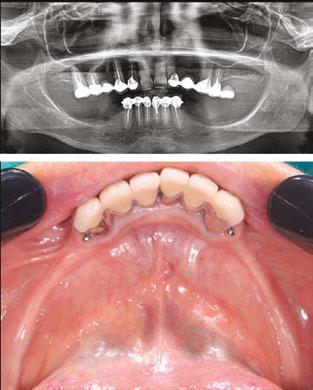

Newer patient-specific implants use modern CBCT and patient scanning technology to create custom-milled patient specific subperiosteal implants. The authors selected Panthera Dental as their partner to design and manufacture this patientspecific subperiosteal implant. Nevertheless, other companies like Bone Easy® and KLS Martin also provide similar implants.

• A cone beam scan exported in DICOM format. The success of the treatment depends largely on the accuracy and quality of the CT data. It is therefore advisable to opt for a large acquisition field, covering the entire mandible up to the posterior ascending ramus. In addition, the highest possible image resolution and the use of metal artifact reduction tools (such as the CS “MAR” — Metal Artifact Reduction) are essential to ensure optimal implant adaptation (Figure 1).7

• An optical impression of the dento-mucosal surfaces.

• This is all combined with a digital wax-up, a preview of the future prosthetic project which will be exported in STL or PLY format. In the case of a limited number of residual teeth, radiopaque markers can be used to help combine the three types of data (Figure 2).8,9

DICOM and STL files are transferred to the Panthera online platform. Once the order has been placed, a viewer allows you to follow and validate the implant creation stages (Figure 3).

Figure 1: Initial CBCT examination (Carestream 9600)

Figure 2: Optical impression (Primescan – Densply Sirona) and prosthetic project based on the antagonist arch (Design4me)

Figure 3: CBCT, optical impression, and digital wax-up uploaded to the Panthera platform dashboard

Figure 4: Subperiosteal implant design on the Panthera Dental platform. (Vestibular, frontal, occlusal, and lingual views)

Lingually, the framework forms a loop in the retro-symphyseal region and stops at the most distally located abutment, remaining coronal to the mylohyoid line (Figure 4).

Thanks to the evolution of materials, the development of digital tools, and the improvement of production techniques, Panthera is able to manufacture subperiosteal implants in grade 23 6AL 4V ELI titanium discs using 5-axis milling machines with a precision of 5 mm. Finally, the surface finish is sandblasted in areas in contact with bone and the periosteum to promote bone regeneration.10.11

Implants are supplied with a 3D resin model of the jaw. This model is used to check that implants fit perfectly before they are inserted. It also helps the operator find the ideal insertion axis, which should be achieved by distal translation followed by mesio-lingual rotation. This movement may differ slightly from one patient to another (Figure 5).

Figure 6 (left): Preoperative situation, panoramic radiograph and intraoral photo. Figure 7 (right): Incisions and flap detachment